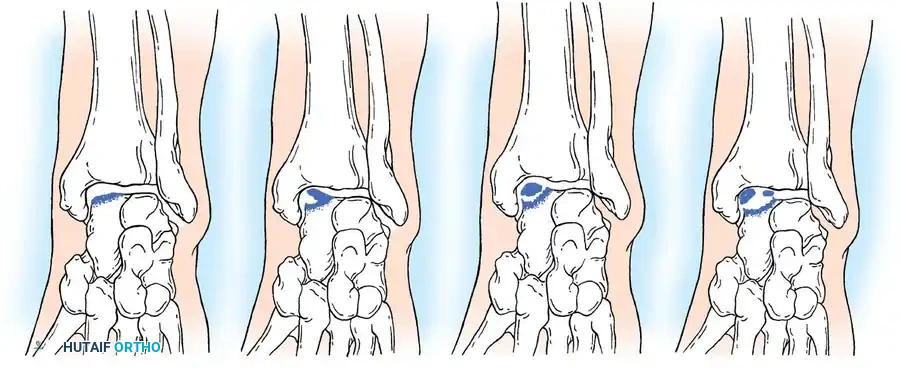

The widely accepted classification system by Berndt and Harty categorizes these lesions into four stages based on radiographic appearance:

- Stage I: A small area of subchondral compression ("blister").

- Stage II: A partially detached osteochondral fragment.

- Stage III: A completely detached fragment remaining within the crater.

- Stage IV: A displaced fragment loose within the joint.

Fig. 33-204 Four types or stages of osteochondral fractures (osteochondritis dissecans of talus). Stage I, “blister”; stage II, elevated fragment but attached; stage III, fragment detached but still in crater; stage IV, displaced fragment.

Morphologically and etiologically, medial and lateral lesions differ significantly:

- Lateral Lesions: Almost exclusively caused by trauma. They are typically thin, wafer-shaped, and resemble acute osteochondral shear fractures. They are more prone to persistent symptoms and degenerative changes.

- Medial Lesions: While many are traumatic, a significant portion have no history of trauma (suggesting true osteochondritis dissecans or ischemic etiology). Medial lesions are typically deep and cup-shaped.

Fig. 33-205 Morphology of medial and lateral lesions. Lateral lesions are typically shallow and wafer-shaped, while medial lesions are deeper and cup-shaped.